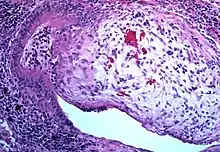

Obliterative bronchiolitis involving the terminal airways

Obliterative bronchiolitis is often diagnosed based on the symptoms of obstructive lung disease following lung injury. The definitive diagnosis is through biopsy, but due to the variable distribution of lesions, leading to falsely negative tests, and invasive nature of this procedure it is often not performed.[6][11] Several tests are often needed to diagnose obliterative bronchiolitis, including spirometry, diffusing capacity of the lung tests (DLCO), lung volume tests, chest X-rays, high-resolution CT (HRCT), and lung biopsy.[11][4]

Transthoracic lung biopsies are preferable for diagnosis of constrictive BO compared to transbronchial biopsies; regardless of the type of biopsy, a diagnosis may only be achieved by examination of multiple samples.[30] Transthoracic biopsies are preferred over transbronchial due to the heterogeneity and distribution of the lesions.[11] OB can be further classified into two categories: constrictive or proliferative.[11] The constrictive pattern is demonstrated by peribronchiolar cellular infiltrates which eventually causes small airway damage and leads to subepithelial fibrosis.[11] The bronchial muscle can eventually become fibrosed which can be identified with trichrome staining.[11] In regards to proliferative disease, intraluminal buds called "Masson bodies" fill the lumen, which results in bronchiolar plugging.[11] Often people with proliferative disease will show butterfly wing-like appearance under microscopy.[11] One key determinate that can be seen on biopsy to differentiate constrictive from proliferative disease is the extent of lesions. Both lesions are localized from the small bronchi to the membranous bronchi, but in constrictive disease the lesions are intermittent while proliferative disease has a continuous distribution.[11]